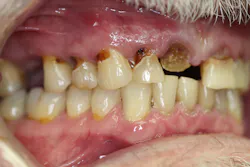

Upon receiving approval from his oncologist to commence with dental care three months later, his examination revealed the following (figures 1-5):

- Severe class III active periodontal disease

- Rampant, generalized cervical caries with some lesions quite extensive in nature

- Broken no. 8 (chief complaint)

- Broken/carious nos. 18, 19, and 30; caries on no. 2

- Generalized dry mouth with white patchy mucosa; he did have a complaint of having a “sticky mouth.” Note: When we took the photos, we had to put water in his mouth because it was so dry.

The genesis for his caries was evident–drug-induced dry mouth and time were the perfect storm for widespread infection that demanded immediate management. Suffice to say, my news to the patient was not welcome.